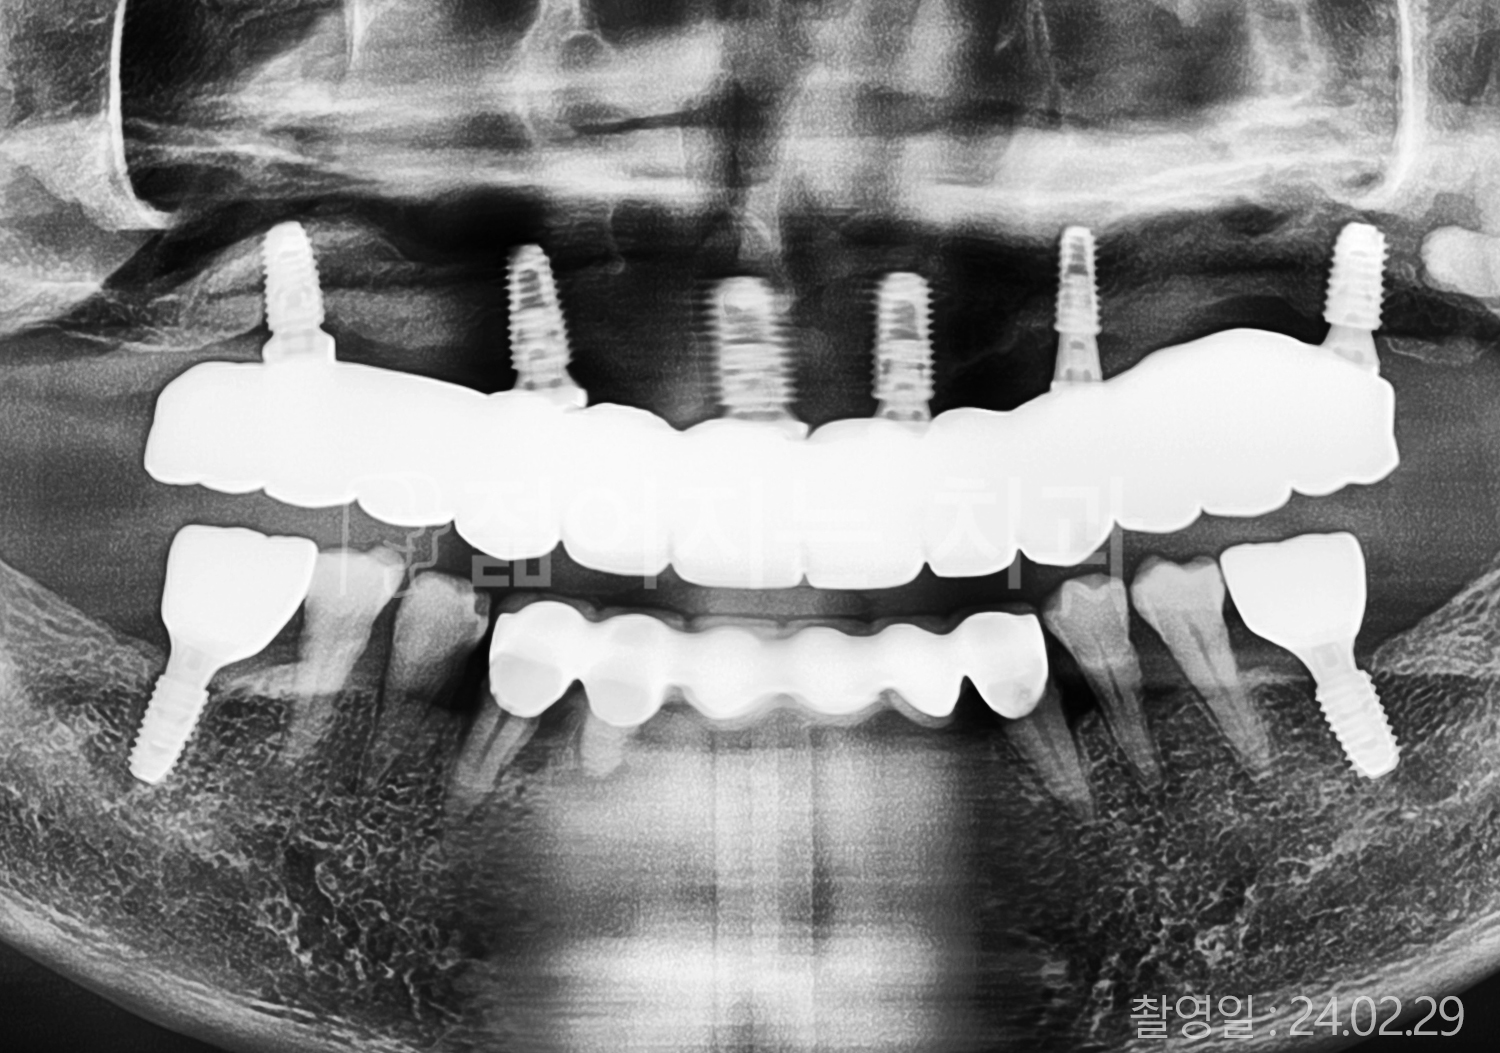

• 40대 전체치아 10개 이상 임플란트

• 50대 전체치아 10개 이상 임플란트